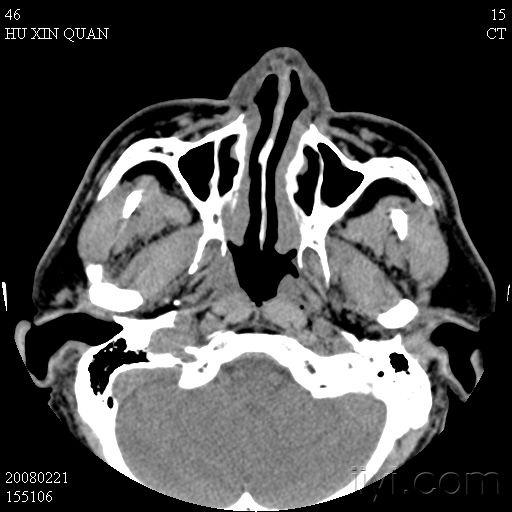

鼻咽癌

图片尺寸1238x1080